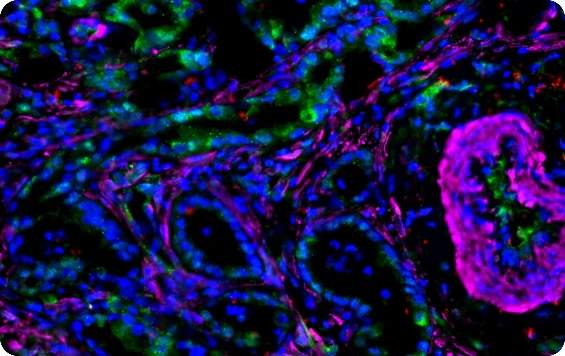

Fluorescence Scanning Features

KFBIO Digital Pathology Slide Scanners (fluorescence) have excellent performance in the accuracy of movement, focus, and image processing, and its accurate whole slide imaging not only meets the requirements of digital slide viewing and operation but is also suitable for AI-assisted image analysis.

Excellent Cross Color Suppression Design

Independent LED light source avoids cross color. High contrast, high brightness, no drift, and no cross color make it more suitable for specific fluorescence channels. Equipped with CHROMA filter narrowband filter, the minimum spectral band resolution reaches 10nm, which can efficiently separates different fluorescence channels to achieve large information density without affecting the quality of data.

High-Sensitivity Cooled Scientific CMOS Camera

Dhyana 400D high-sensitivity refrigeration scientific CMOS camera is equipped, low signal-to-noise ratio and high resolution, with a new 1.2 inch surface array scientific CMOS chip. The quantum efficiency at 600 nm is up to 80%. 6.5 μm pixel size and 2*2 pixel binning function realized by FPGA, suitable for low-light detection and imaging. The Dhyana 400D has excellent performance, with only 2 electrons of readout noise. The browsing speed is up to 35 frames/s at 4 megapixels. And the data transmission speed is up to 5Gb/s to provide strong support for users’ work.

Multiplex immunofluorescence scanning

Tumor micro environment analysis/

spatial transcriptome analysis